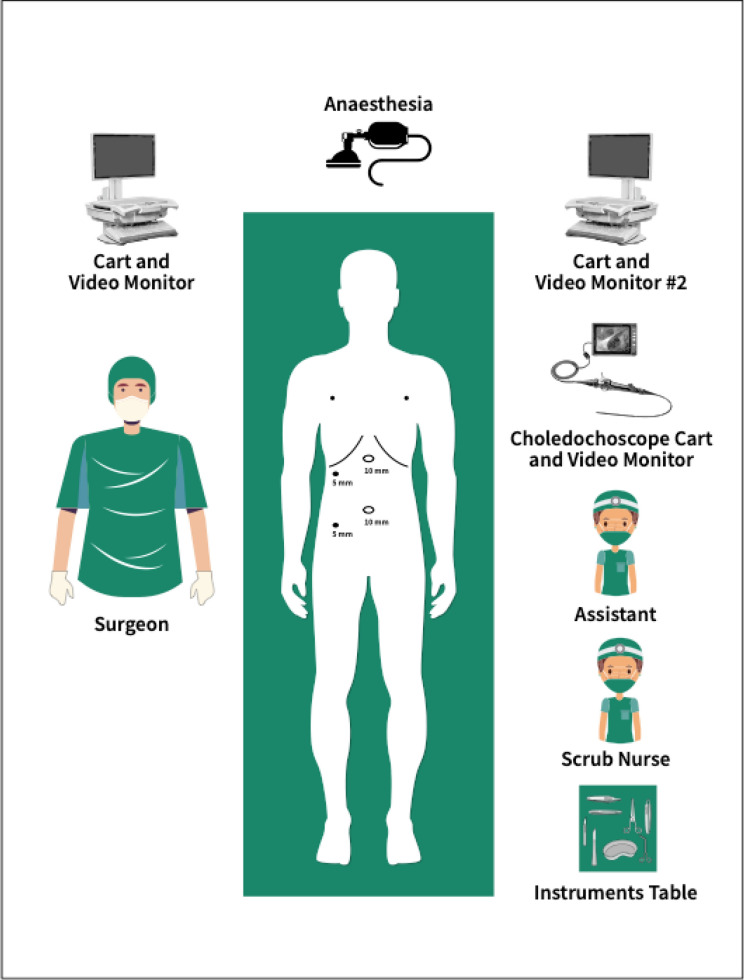

The operation commenced as per a routine laparoscopic cholecystectomy. The cystic duct and cystic artery are dissected in Calot’s triangle to obtain the critical view of Strasbourg. A cystic duct opening is then made with a laparoscopic scissors for cannulation with a catheter for cholangiography. Once choledocholithiasis is confirmed, the operating room is set up as per (Fig. 1). The diameter of the cystic duct is then assessed at this point and a decision is made if the 3 mm or 5 mm choledochoscope is utilized for cannulation.

Cannulation of the cystic duct stump with the choledochoscope is performed through either an extra 5 mm port just under the right subcostal margin or with one of the existing working ports. Once in the common bile duct (CBD), the choledochoscope will be pushed distally towards the ampulla. If this step is difficult, then a Jagwire (Boston Scientific) is passed first through a cholangiogram catheter to facilitate passage of choledochoscope as a (Seldinger) technique. Once the stone(s) identified, it will be captured and removed using a Nitinol 1.5F, 1.7F or 1.9F basket, passed down through the working channel of the choledochoscope.